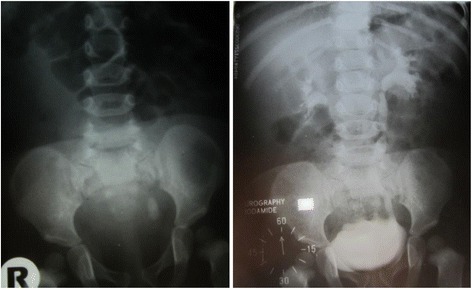

On physical examination the child appeared mildly dehydrated with increased body temperature of 37.6 °C. A laboratory examination found moderate anaemia (haemoglobin 93.0 g/l), leucocytosis (15x109/l) and moderately elevated CRP (42.6 mg/l). Serum electrolyte, urea and creatinine levels were normal. The calcium/creatinine ratio and 24 h calcium excretion was within the reference range. Blood gas analysis was normal with no evidence of metabolic acidosis. Ultrasonography of the abdomen raised suspicion of ureterolithiasis l.sin. Cystourethrography was indicated, showing concrement sized 2 cm x 0.8 cm in the distal part of the left ureter with mild dilatation of the renal pelvis and ureter (Fig. 1).

Fig. 1.

X-ray findings of urolithiasis in patient with PH2

At the age of 11 months, an ureterolithotomy was performed at the University Children Hospital Bratislava. A chemical analysis of the extracted stone was performed, and the stone was characterised as a composite of virtually pure calcium oxalate. The following course was without any complications.